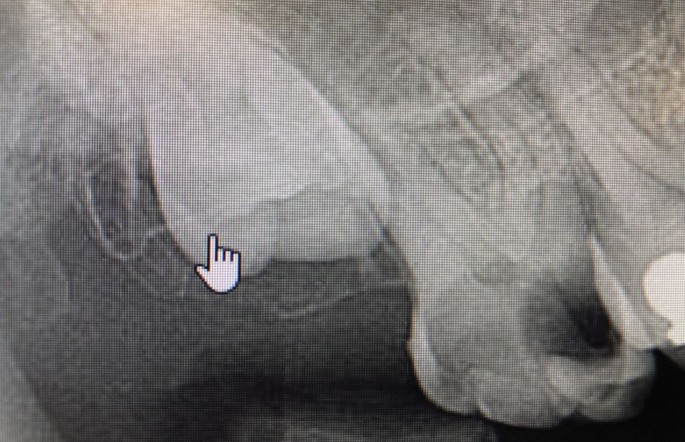

Risk factors: Lone standing upper molars, pneumatised antra, sclerotic bone, older patients, >50% of the root(s) overlying the antrum, discontinuity of the PDL space/lamina dura, poor surgical technique, presence of antral pathology (Fig. 1).

Preoperative radiograph showing a grossly carious 17 adjacent to an unerupted 18. The antral floor appears to lie about halfway down the roots of the 17